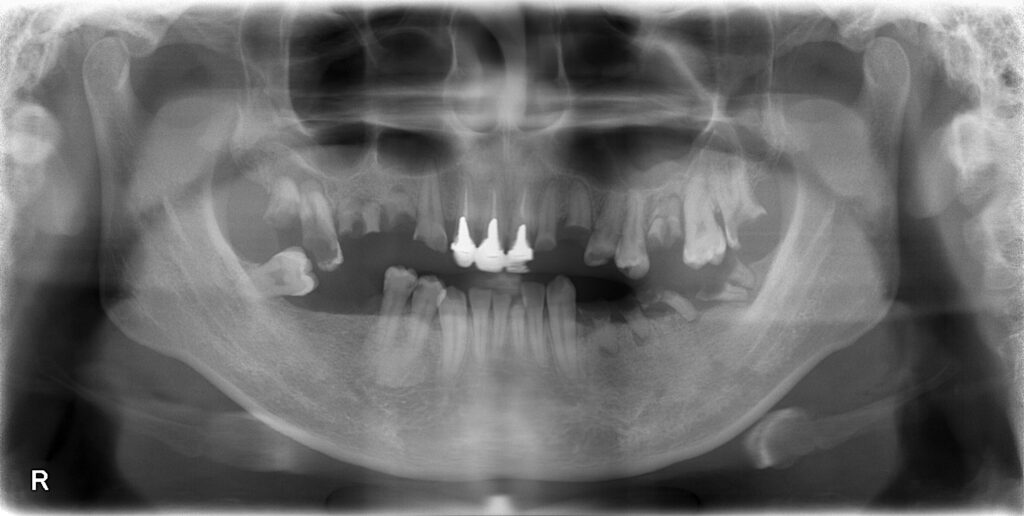

まずは初診時のレントゲン所見です。

【初診時のレントゲン】

全体的に抜歯が必要な歯牙が多く、食事は前歯でなんとか行っている状態です。

最初のレントゲンと比較するとかなり状況が改善されております。